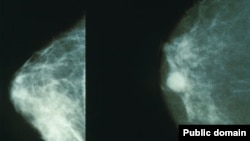

Маммограф аппараты: оӊ жактагы сүрөт соо, сол жактагы залалдуу шишик менен ооруган аялдын көкүрөгү